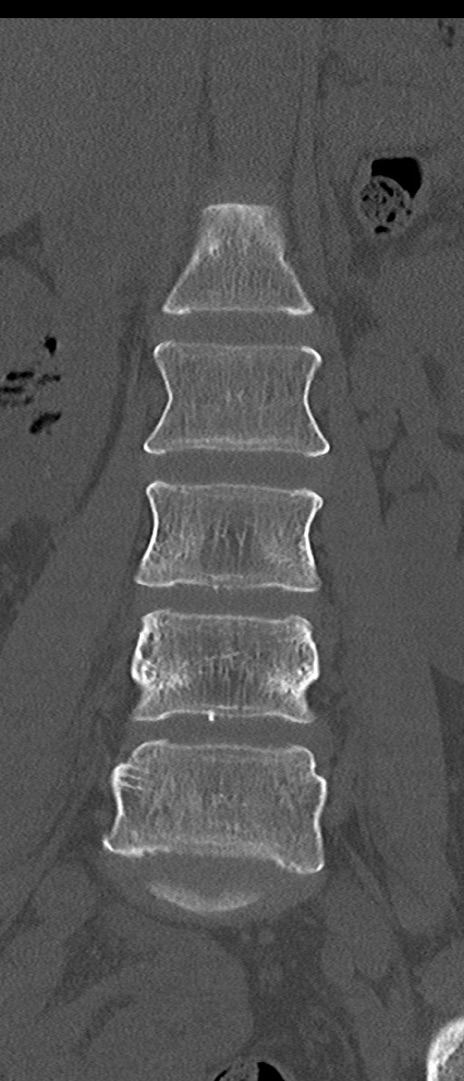

【整形】TIPS症例4 腰椎CT(冠状断像)

腰椎CT